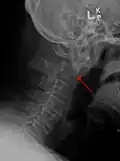

Fractures of the dens are classified into three categories according to the Anderson Alonso system:

- Type I fracture - Extends through the tip of the dens. This type is usually stable.

- Type II fracture - Extends through the base of the dens. It is the most commonly encountered fracture for this region of the axis. This type is unstable and has a high rate of non-union.

- Type III fracture - Extends through the vertebral body of the axis. This type can be stable or unstable and may require surgery.[1]

Type 2 dens fracture